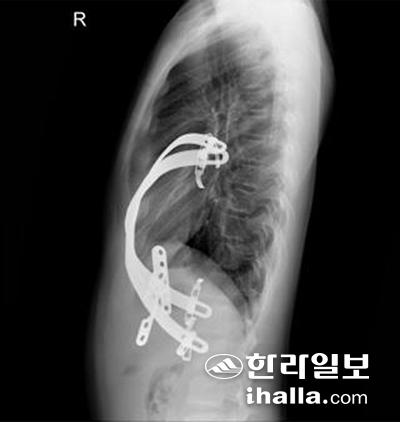

제주대학교병원에서 수술 받은 환아 B의 흉부외관 및 수술 후 X ray에 삽입돼 있는 막대가 선명하게 보인다.

오목가슴의 수술적 교정은 보통 '너스(Nuss) 수술법'으로 치료한다. 양 옆구리 부위를 1㎝가량 절개한 뒤 교정용 금속막대를 넣어 함몰된 가슴뼈를 들어 올려 교정하는 방식이다. 이렇게 넣은 금속막대는 가슴뼈 교정 후 2~3년 뒤에 제거한다. 하지만 이 수술법에도 문제가 있다. 탁월한 미용효과로 환자들의 만족도가 높았지만 삽입된 금속막대가 고정되지 않고 움직여 수술이 실패하거나, 재수술이 필요한 경우가 빈발한 것으로 알려졌다.

최근에는 이런 문제를 해결할 수 있는 치료법으로 옆구리에 넣는 막대를 두 개 내지 세 개 삽입하고 서로 연결하는 '교량판'을 이용해 막대가 움직이는 것을 봉쇄하는 방법도 제시되고 있다.